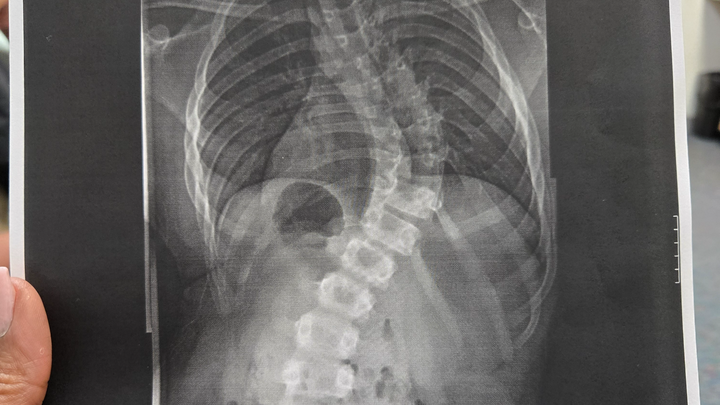

Our youngest son, Ian, has been diagnosed with severe scoliosis and is requiring a major spinal surgery due to his continuous back pain. He is a wonderful and active 12-year-old that has been dealt a crappy hand, but we—his family—are his backup. He has worn a sleeping back brace since January; however, this did not improve his pain level or slow down the curvature. So he now has a 70° curve, but he was only at a 47° curve at the beginning of the year. He has now been prescribed a daytime brace to give him a little relief at school, but that still will not take his pain away. We have been working with his school to accommodate him wherever possible, but his pain has caused him to miss a number of days from school. So now, homebound care is the next step until his surgery and recovery is complete, so that he doesn't fall behind in his schoolwork.